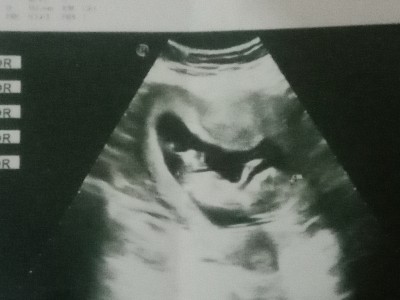

Kontrol e gittim geçenlerde doktor göstermiyor cinsiyeti dedi çok meraklı biriyim 1 oğlum var bu seferki kız olsun istiyorum yardımcı olup cinsiyet tahmininde bulunur musunuz ☺️

Gebelik haftası 13+4